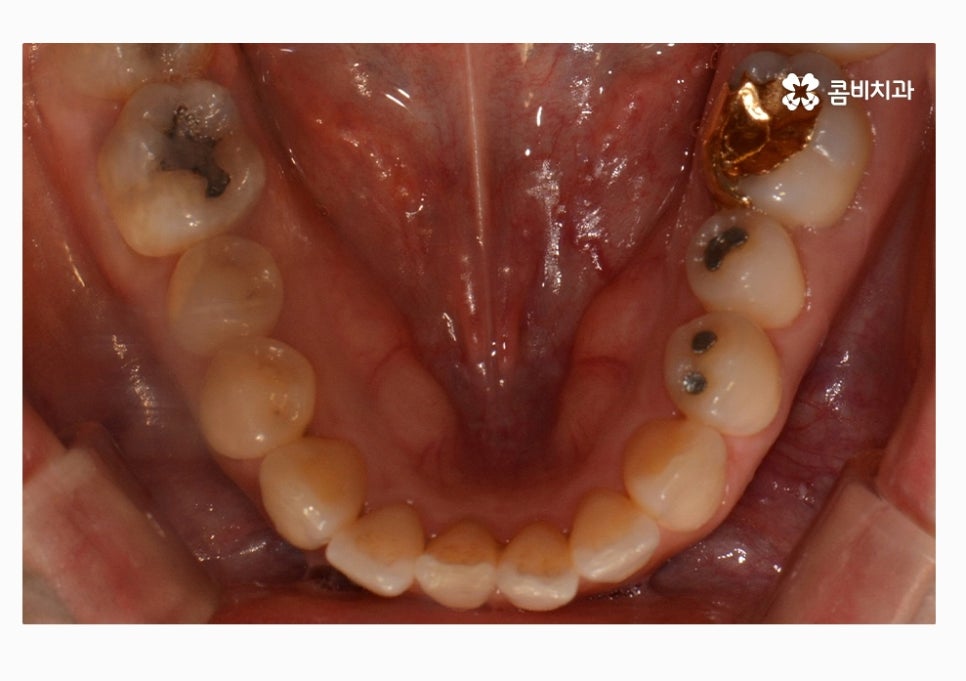

부정교합의 종류도 다양하지만 오늘 보시는 케이스의 경우

절단교합 + 3급부정교합에 해당하며 아랫니가 과하게 앞으로

돌출된 경우에는 치열뿐 아니라 주걱턱과 같이

얼굴형에도 영향을 줄 수 있어요.

청결 관리가 제대로 되지 않아서 충치 및 잇몸질환이

발생할 가능성이 높아질 수 있는데요.

치아끼리 부딪히면서 시간이 지남에 따라 치열이 더 틀어지거나

구강 관리가 잘되지 않아서 충치나 치주질환이

발생할 가능성이 높아지는 경우를 많이 볼 수 있어요.